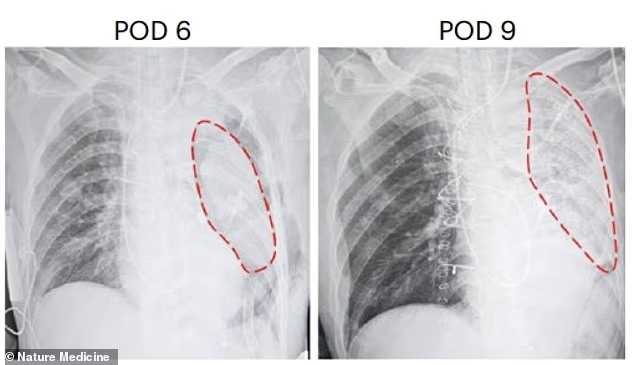

චීනයේ ශ්වසන රෝග සඳහා වූ ජාතික සායනික පර්යේෂණ මධ්‍යස්ථානයේ පර්යේෂණ කණ්ඩායම, ජාන සංස්කරණය කරන ලද ඌරෙකුගේ වම් පෙණහලුව 39 හැවිරිදි පුද්ගලයෙකුට බද්ධ කරනු ලැබුවා.

මෙහිදී සොයාගනු ලැබුවේ එම සත්වයාගේ පෙනහළු මිනිස් සිරුර විසින් පිළිගෙන දින නවයක් සක්‍රීයව ක්‍රියාකර ඇති බවයි.

කෙසේ වෙතත්, බද්ධ කිරීමෙන් පැය 24 කට පසු පෙනහළු හානිවීමේ සලකුණු සහ තුන්වන සහ හයවන දිනවලදී ඉන්ද්‍රිය ප්‍රතිදේහ මඟින් ප්‍රතික්ෂේප කිරීමේ සලකුණු පර්යේෂකයන් නිරීක්ෂණයට ලක්ව තිබෙනවා.

නවවන දිනයේදී ඔවුන් අත්හදා බැලීම අවසන් කර ඇති අතර මෙම සොයාගැනීම් ඌරෙකුගෙන් මිනිසෙකුට පෙනහළු බද්ධ කිරීමේ පළමු පියවර නියෝජනය කරනු ලබනවා.